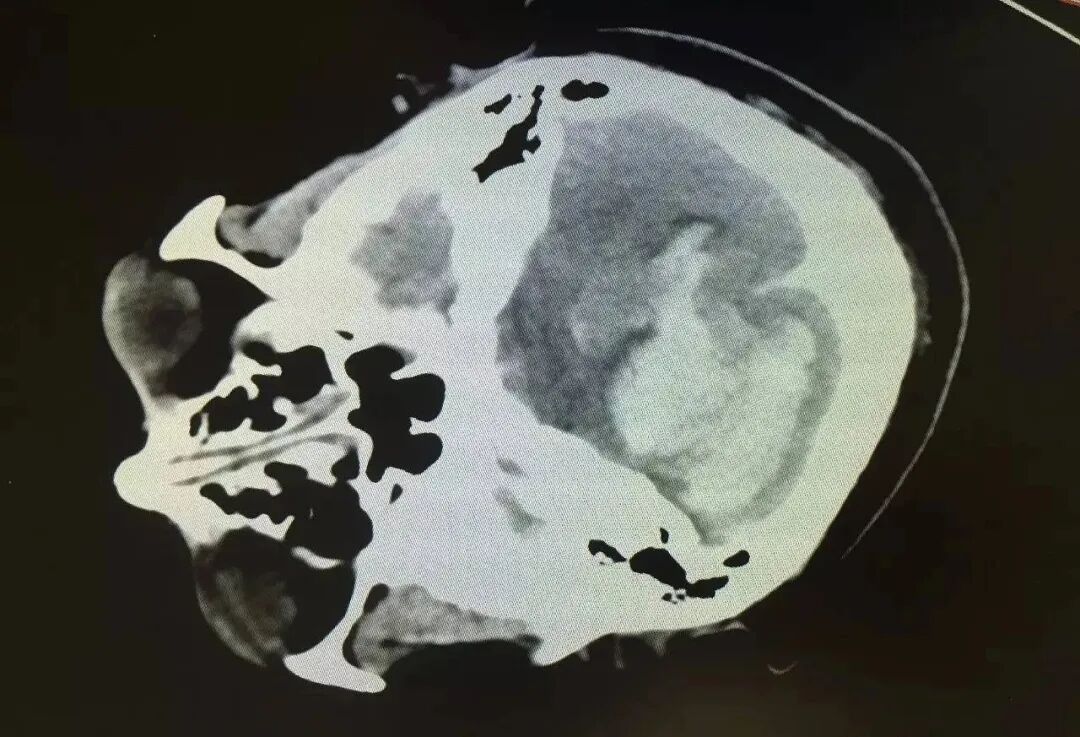

患者张先生,67岁,男性,退休工程师。两年前,张先生被诊断为小脑萎缩。他主要出现步态不稳、头晕、言语含混不清等症状。经过西医常规治疗,效果并不明显。后经病友介绍,他找到了盛劲强大夫。盛大夫认为,小脑萎缩属于“痿证”范畴,其病机主要为肝肾不足、筋骨失养、脉络瘀阻。针对张先生的症状,中医辨证为肝肾阴虚、瘀血阻络。治宜滋养肝肾、活血通络。随后选用“补髓健脑汤”疗法进行治疗。

治疗过程中,张先生坚持服药3个月,症状明显改善。步态较前稳定,头晕发作频率降低,言语表达清晰度有所提高。复查头颅MRI显示,小脑萎缩程度较前减轻。中药治疗效果得到了患者和家属的肯定。患者为巩固病情不让其继续发展,甚至抱有好转的心思,继续服用。六个疗程后,症状基本改善,身体有力气了,自己可以适当性地做一些运动,走路比以前稳多了,还在积极治疗中。